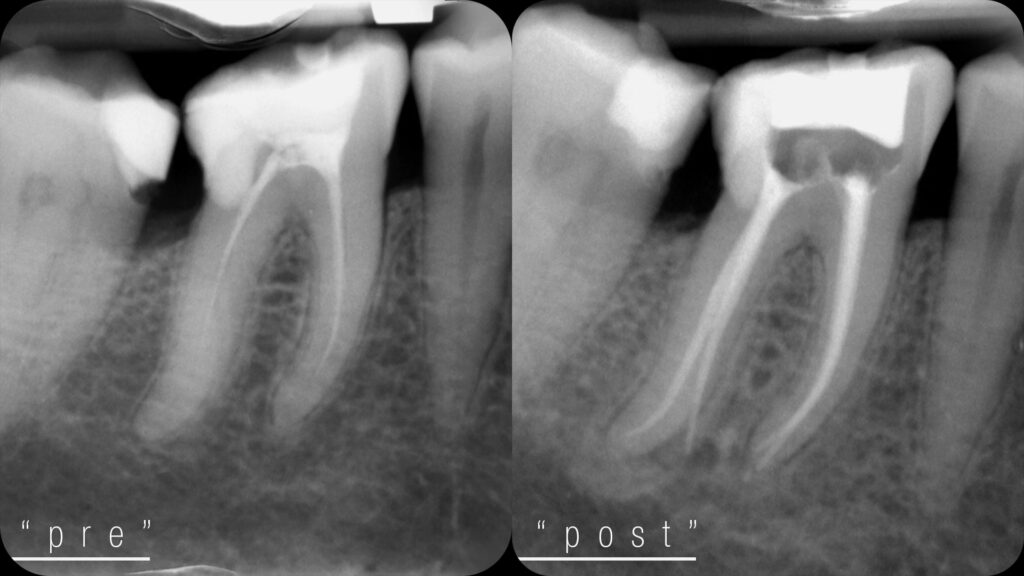

- Localizzatore apicale: ci indica con precisione fino a dove intervenire, evitando errori e trattamenti inutili.

- Motore endodontico: pulisce e sagoma i canali in modo efficace e controllato, riducendo i tempi alla poltrona.

- System B: sigilla i canali con guttaperca riscaldata, adattandosi perfettamente alla forma interna del dente.

- Siringa Obtura: consente una chiusura omogenea anche dei canali più complessi, per una terapia stabile e duratura.